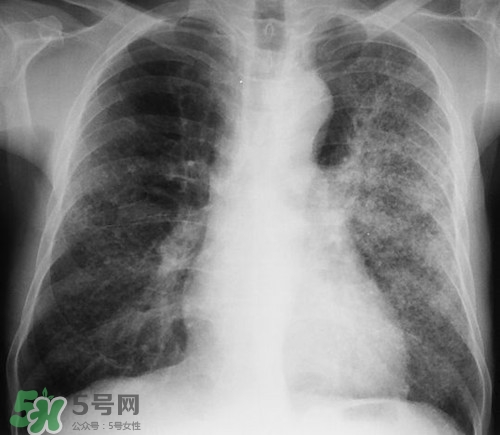

肺炎是常見的呼吸道感染疾病,這病也確實麻煩,如果處理不當可能危及生命哦,那么肺炎會不會傳染呢?吃什么好的快呢?下面我們來介紹下吧!